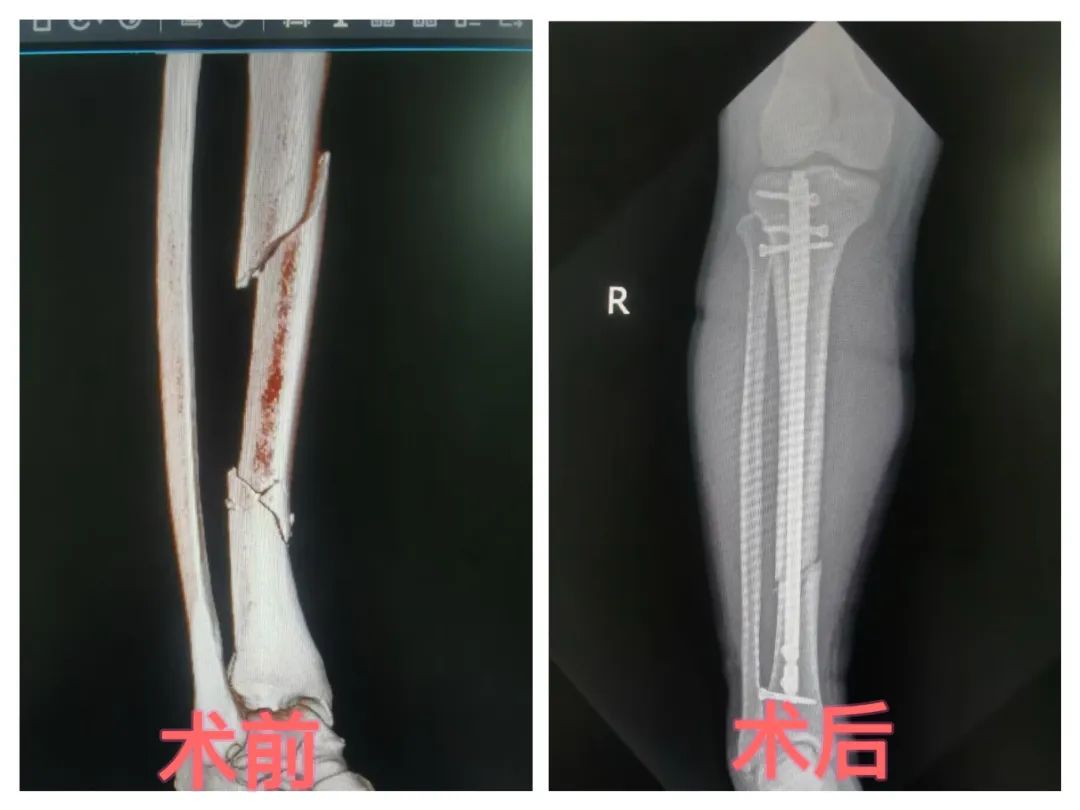

胫骨骨折怎么办?万医髌上入路胫骨髓内钉内固定微创手术,让您的康复更轻松!

传统手术带来的大切口、漫长恢复期总让人望而却步。为减轻胫骨骨折患者治疗痛苦,铜仁市万山区人民医院骨二科主任罗杨带领科室手术团队,采用“髌上入路胫骨髓内钉内固定术”的微创方式为多名胫骨骨折患者进行手术,重塑患者骨骼健康。微创手术以创新技术颠覆传统治疗模式,为患者带来创伤小、恢复快、效果优的全新康复体验!

胫骨骨折微创手术借助高清影像设备(如C型臂X光机、3D导航系统)精准定位骨折部位,通过2-3厘米微小切口,采用髓内钉固定、经皮钢板置入等先进技术复位骨折断端,无需大面积切开肌肉和软组织,就能实现骨折部位的稳定固定,为骨骼愈合创造良好条件。

5. 精准复位,效果佳:在影像设备引导下,医生能更精准地完成骨折复位与固定,确保骨骼恢复原有解剖结构,提高骨折愈合质量。